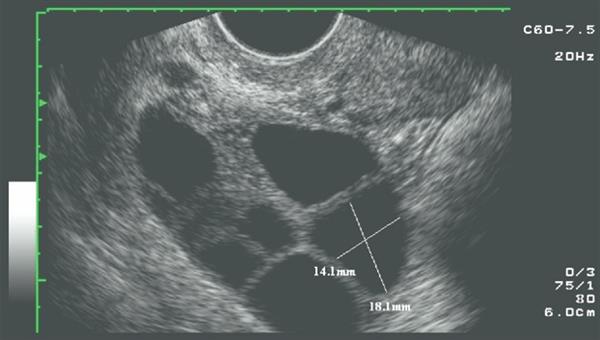

一般基础卵泡在20以上且年轻的试管备孕准妈妈较为容易出现。出现腹水使的腹腔内积存许多液体,准妈妈会明显感觉到腹部微微鼓起,并伴随一些不适症。

中度卵巢过度刺激综合征表现为恶心呕吐、腹胀加重、腹痛、呼吸急促,但无显著液体丢失及电解质平衡失调的表现,检查可见腹部膨隆但无腹肌紧张。

重度卵巢过度刺激综合征表现为腹腔内积液众多,尿少,水电解质平衡紊乱,卵巢明显增。此时准妈妈必须要住院处理。如果处理不及时,可能就会危及生命安全。